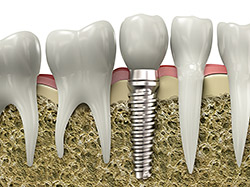

Implant Restoration

If you have missing teeth, it is crucial to replace them. Without all your teeth, chewing and eating can destabilize your bite and cause you discomfort. When teeth are missing, your mouth can shift and even cause your face to look older. Implants are a great way to replace your missing teeth, and if properly maintained, can last a lifetime!

An implant is a new tooth made of metal and porcelain that looks just like your natural tooth. It’s composed of two main parts: One part is the titanium implant body that takes the place of the missing root, and the second part is the tooth-colored crown that is cemented on top of the implant. You can smile confidently knowing no one will ever suspect you have a replacement tooth.

In addition to tooth replacement, implants may be used to anchor dentures, especially lower dentures that always tend to shift when you talk or chew. For patients with removable partial dentures, implants can replace those missing teeth so you can get rid of the partial denture and have a more comfortable and natural-looking smile.